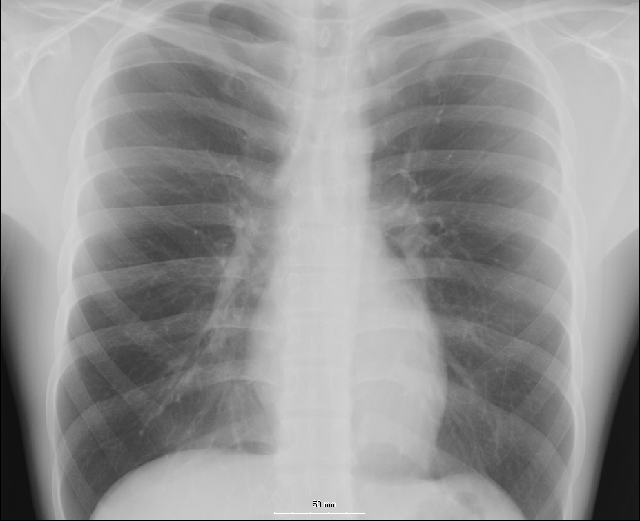

"We have three months of X-rays here," I said, "and the spot seems to be the same size in each. If it is cancer, shouldn't it be getting larger?"

That's what we did. Six months later the spot was still there, the same size. "It looks like scar tissue," he said, "it wasn't there two years ago so I would have to say you must have had a pneumonia or other pulmonary issue between then and now."